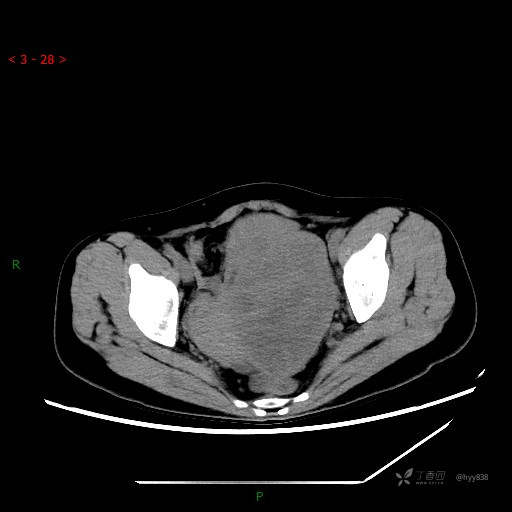

增强动脉期